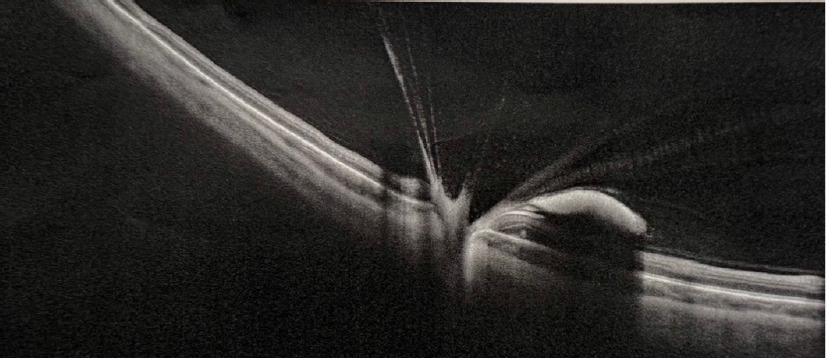

Postoperative visual acuity was 5/5 binocularly with IOP measurements 15 mmHg in OD and 16 mmHg in OS. During the follow-up visit, one month after the procedure, a comparative image was taken during the fundoscopic examination of the left eye (Figure 4), and an OCT examination of the left eye was also performed (Figure 5).